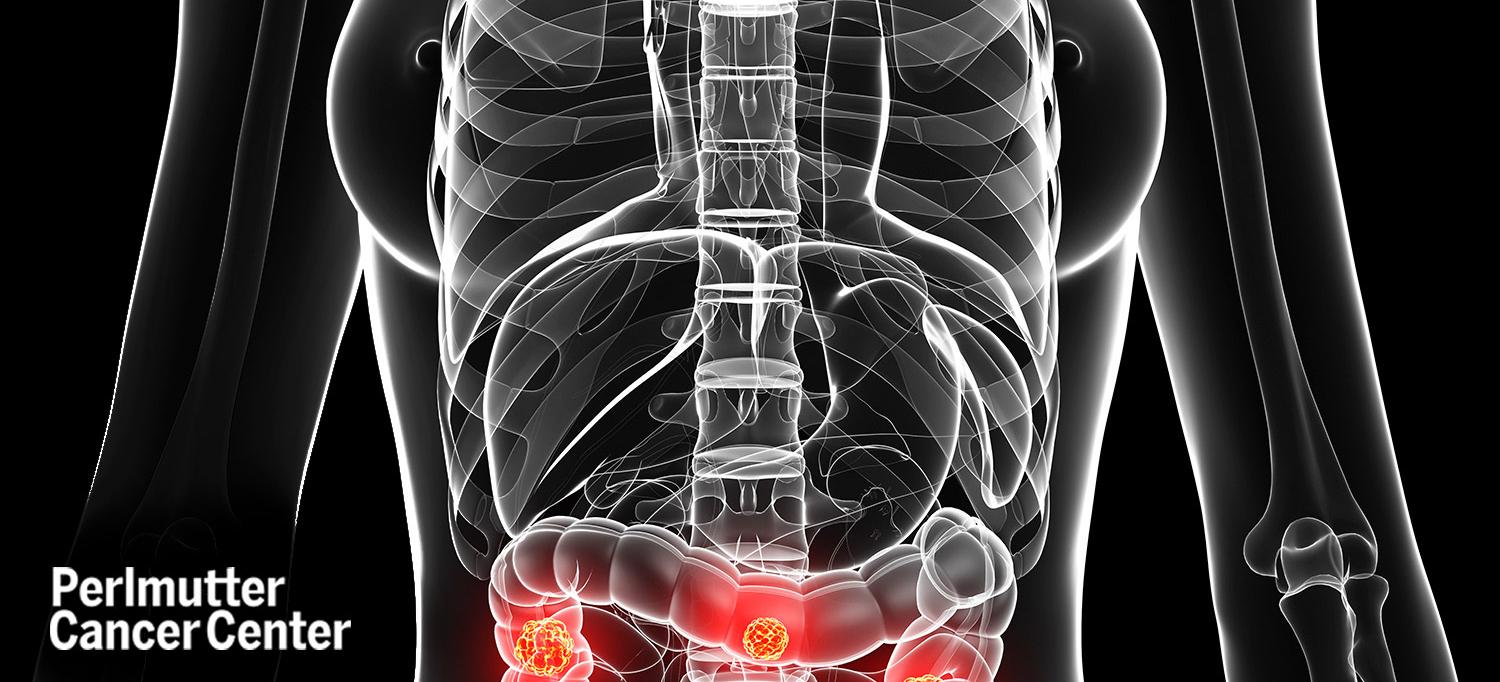

A diagnosis of colon cancer can be overwhelming. Paul E. Oberstein, MD, an assistant professor in the Department of Medicine and director of the Gastrointestinal Medical Oncology Program at NYU Langone Health’s Perlmutter Cancer Center, shares some tips with HealthCentral to help people with colon cancer to better cope with their diagnosis.